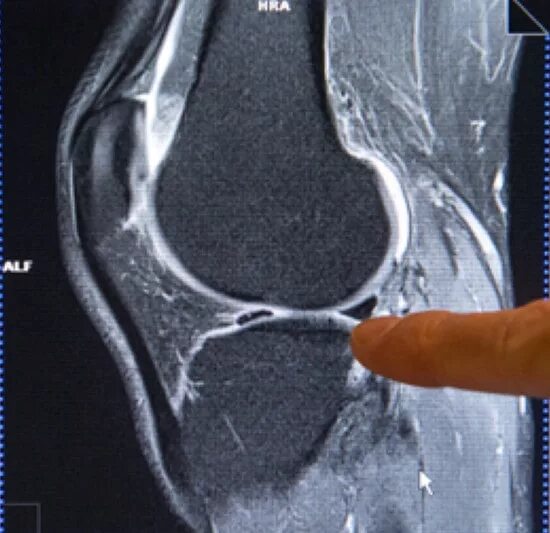

Гонартроз мрт